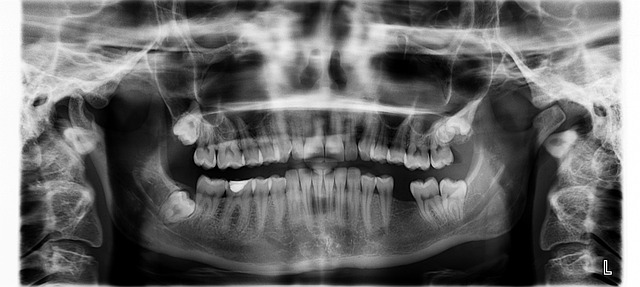

The power of preventive care lies in its ability to nip potential problems in the bud. Regular check-ups, cleanpings, and x-rays can reveal early signs of decay or gum disease, allowing for timely interventions. For instance, addressing tooth sensitivity or mild discoloration promptly could prevent more severe issues down the line. This proactive strategy not only saves time and money but also ensures that patients maintain healthy, vibrant smiles over the long term.